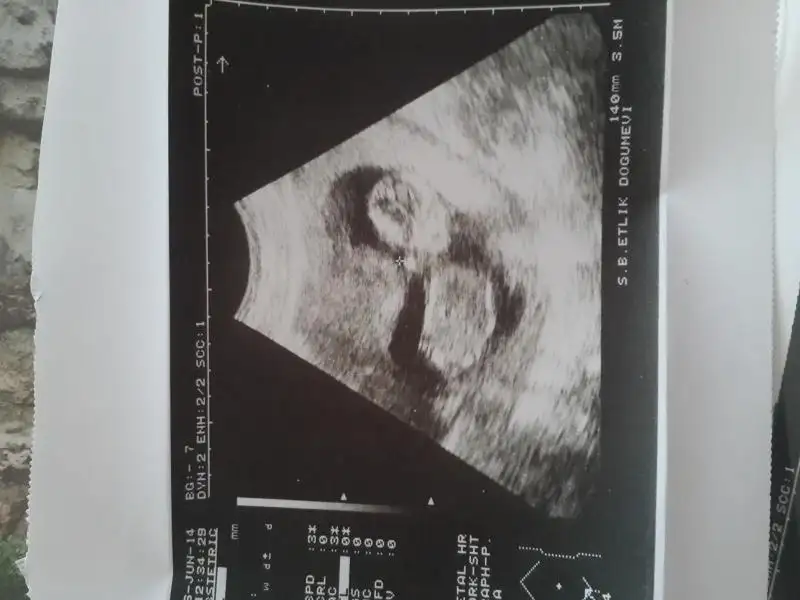

kafatasına bakilirsa kesin erkek.. üstteki daha ufak sanirim ama bi cikinri var hafif yukarıya doğru.. ikinci usg de bacak arasinda dokuluk var görünen o beyaz şey kız bebekte bos ya da ince çizgi halinde oluyor..